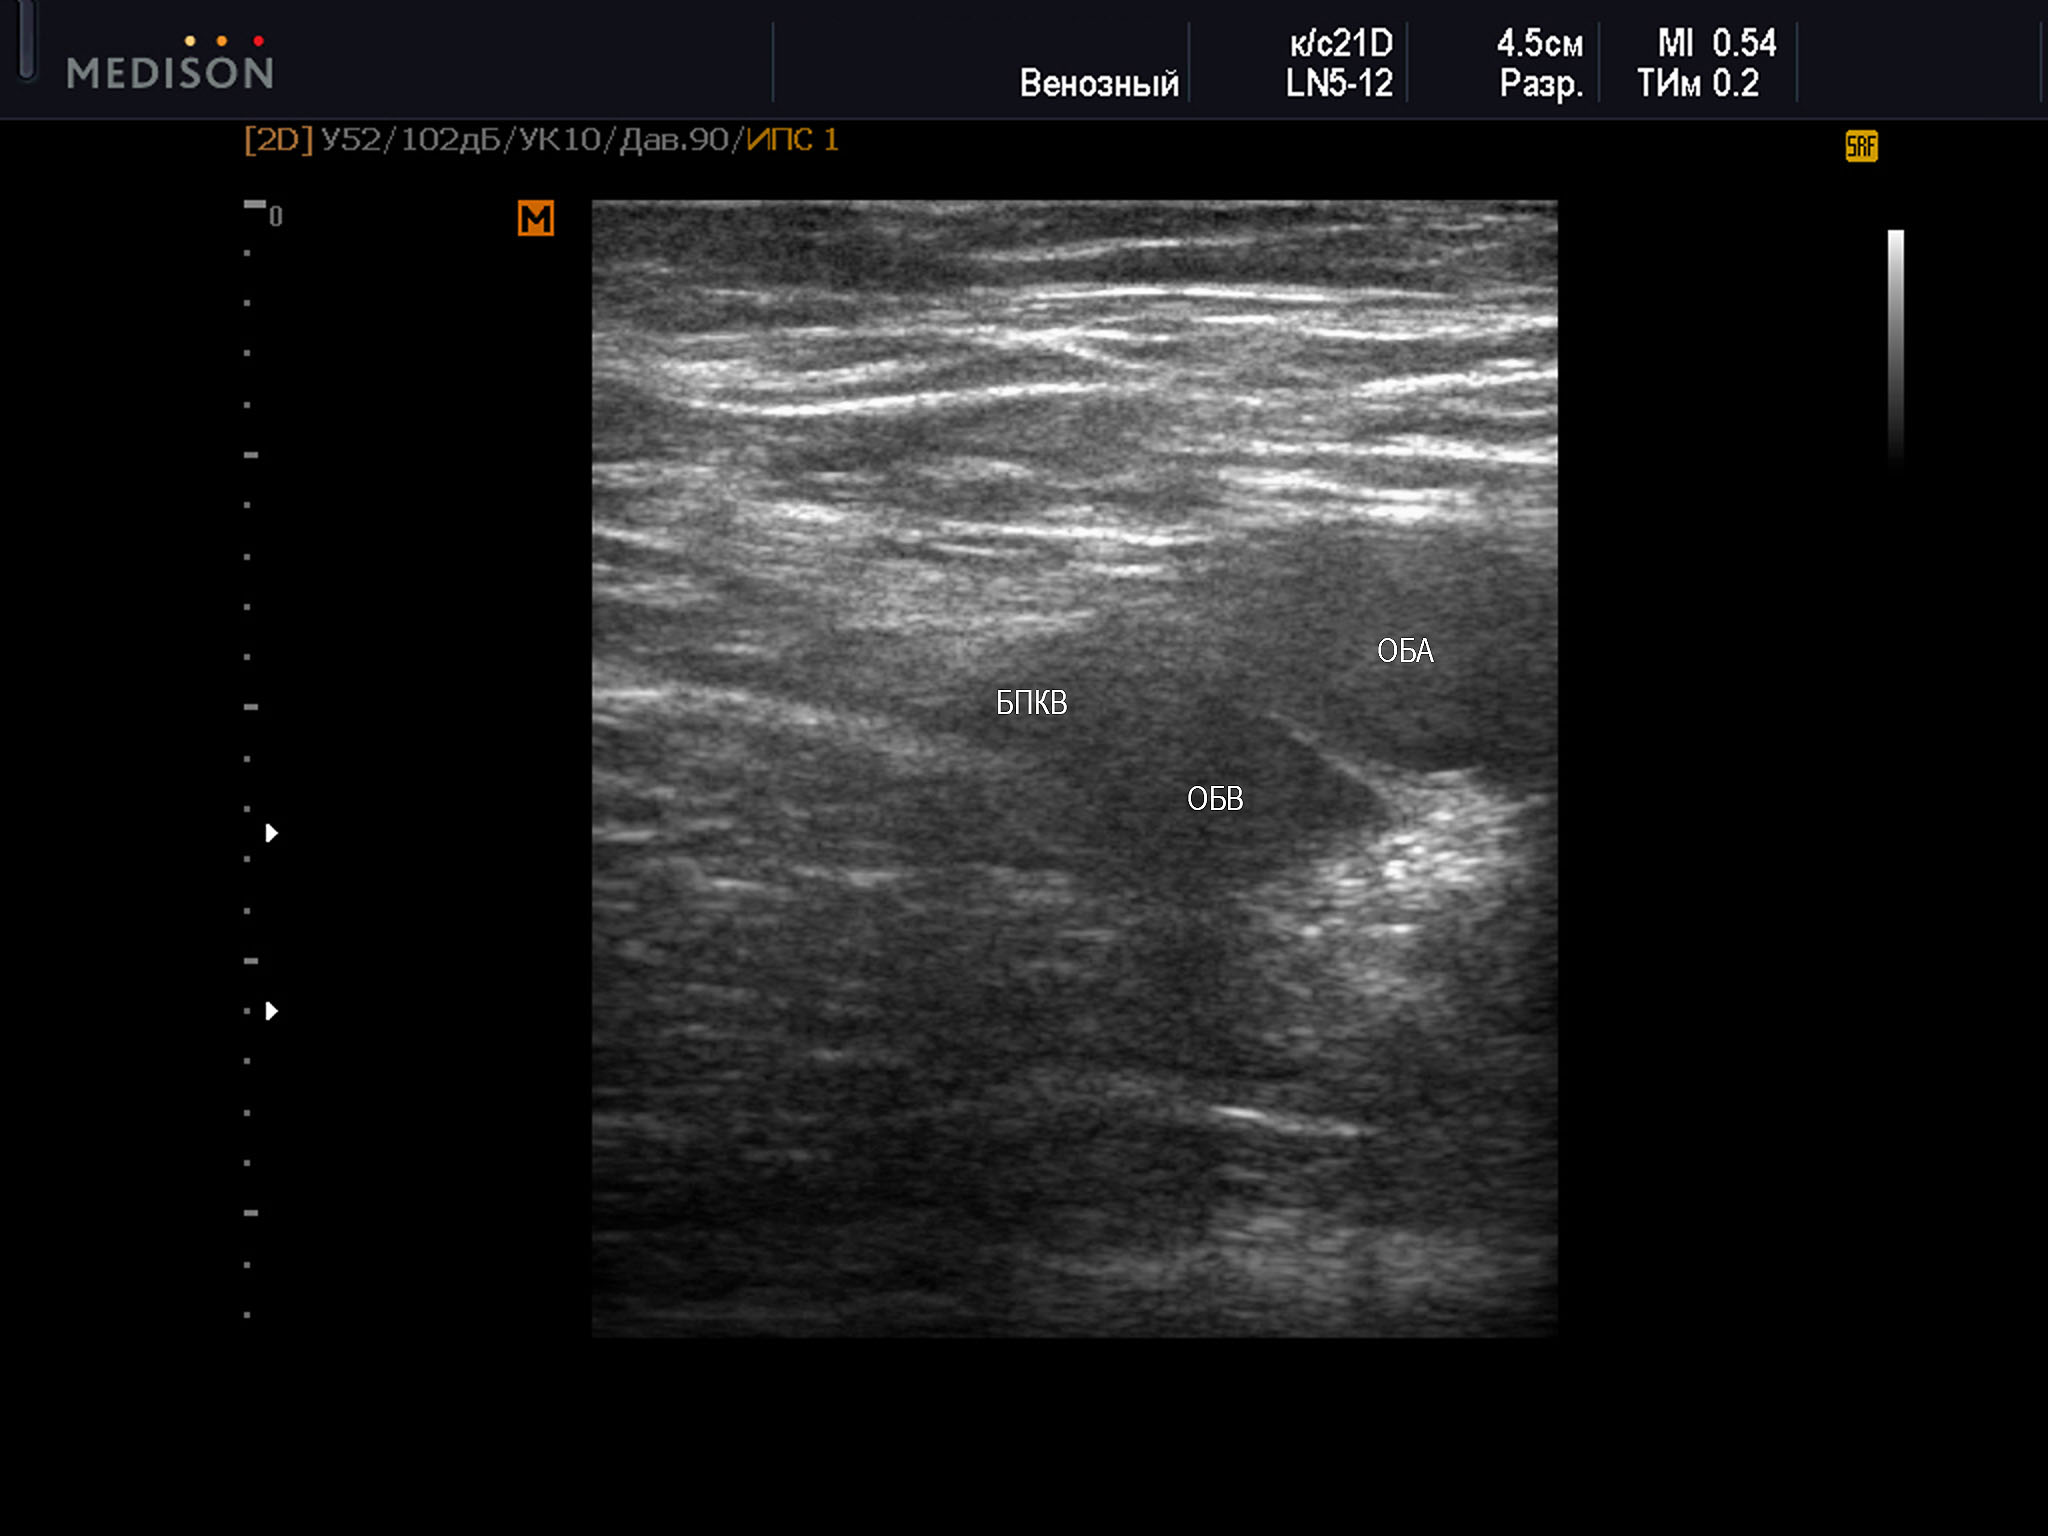

1 тип характеризовался полным прикрытием ствола бедренной веной за счет артерии (рис. 1):

Пример диагностического ультразвукового изображения на уровне верхней трети бедра, поперечное сечение общей бедренной вены и общей бедренной артерии, Тип 1 взаимного положения сосудов

SonoAce R7, линейный датчик, женщина, 69 лет.

ОБА – общая бедренная артерия; ОБВ – общая бедренная вена; БПКВ – большая подкожная вена бедра